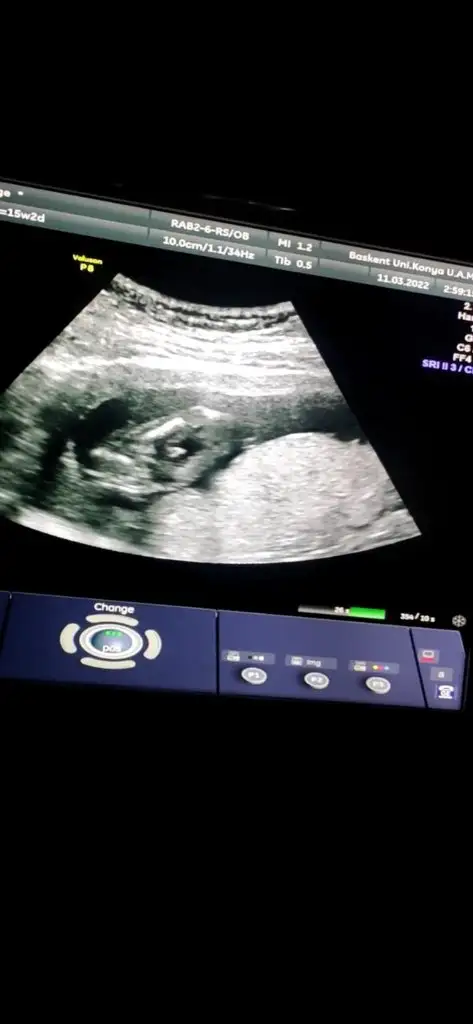

Ben bişey anlayamadım nuba göre benim ne oluyor acabaCumartesi cinsiyet öğreneceğim o yüzden bütün teorileri araştırırken bu karşıma çıktı bana mantıklı geldi gibişöyle ki omurgadan popoya doğru giden çizgi sonda yukarı doğru çıkıyorsa erkek, düz gidiyorsa kız oluyormuş fotoğraf ekleyeceğim orda daha ayrıntılı gösteriyor

Dr da öyle dedi emin olamadı alttan bakınca da kıza benziyor dediAyy maşallah ne güzel çıkmışsanki şu işaretlediğim yerde yukarı doğru bir çıkıntı varmış gibi geldi bana Öyle olunca da erkek deniyor ama bilemiyorum tamamen benim yorumum